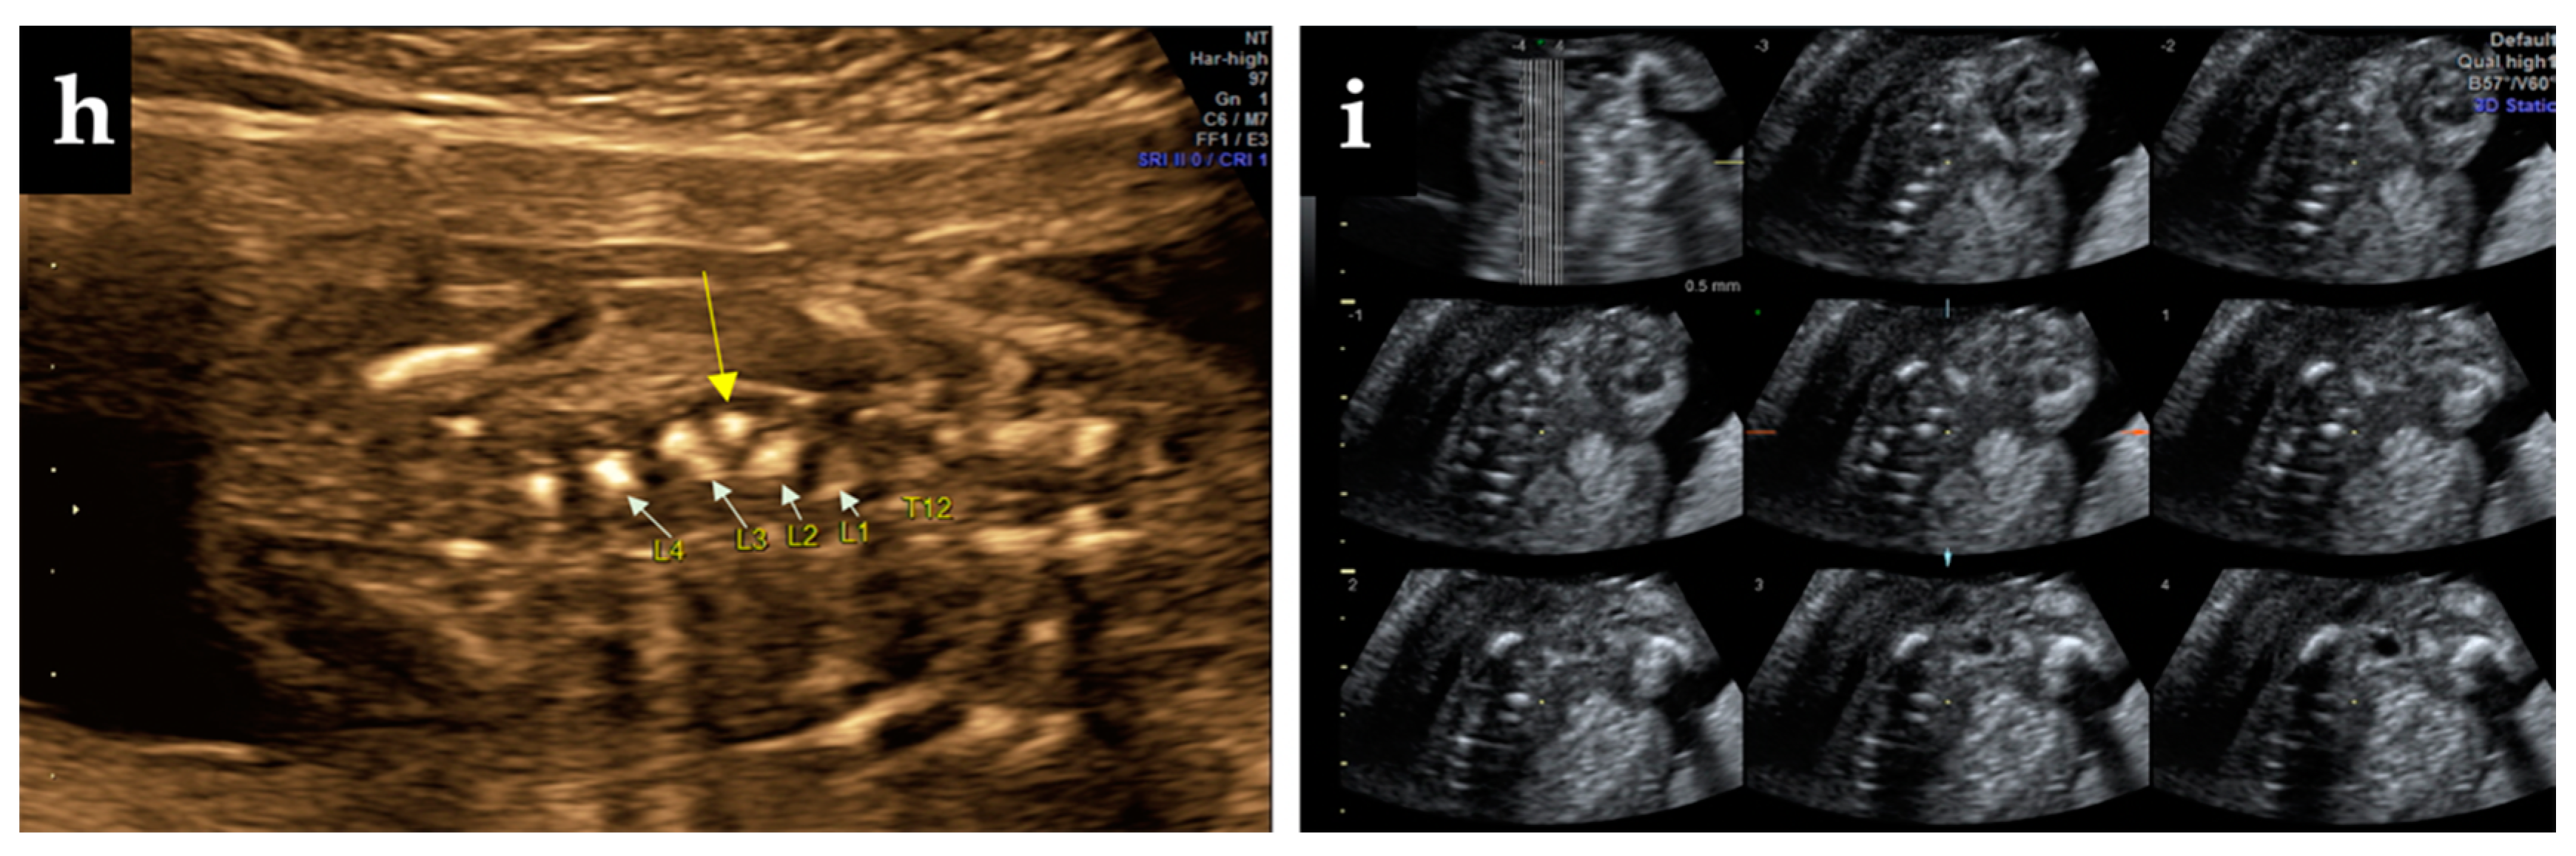

Figure 1.

Ultrasound findings: (a) suspect angulation of the thoracolumbar spine at 12-weeks show the hemivertebrae (yellow arrow), (b) zoom-in above the hemivertebrae in 3D static reconstruction, (c) image of the whole spine at 12-weeks; (d) clear 2D imaging of the hemivertebrae; (e,f)—US scans of the fetal spine at 16 and 23 weeks, (g) tracing the correspondence of the vertebrae lateral ossification centers, (h) numbering and positioning of the vertebrae at 23 weeks on 2D ultrasound sepia mode, (i) Tomographic Ultrasound Imaging (TUI)—successive scans of the spine revealing the anomaly.